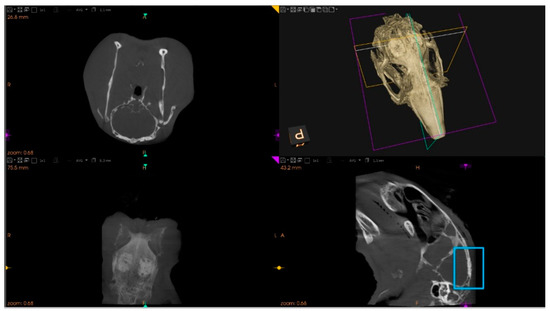

2.7.1. Microtomographic Evaluation

3.2. The Bone Healing in Rabbit Calvarial Critical Size Defects

3.3. Secretome Modulation of the Bone Healing Process